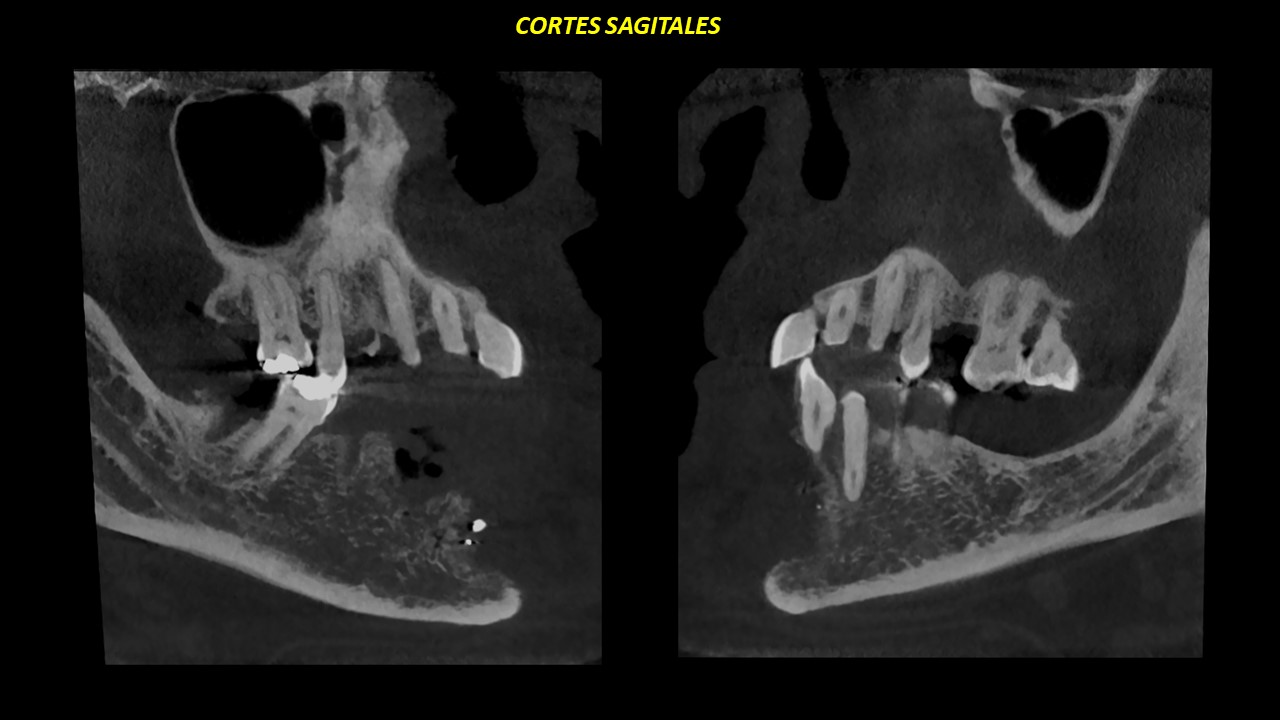

Figura 4

En cortes sagitales (Figura 4), se aprecia el compromiso y borramiento de las corticales del conducto dentario inferior derecho; así como del foramen mentoniano.